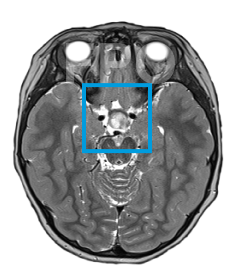

The first and only type II RAF inhibitor for BRAF alterations in relapsed or refractory pediatric low-grade glioma (R/R pLGG)1

OJEMDATM (tovorafenib) is indicated for the treatment of patients 6 months of age and older with relapsed or refractory pediatric low-grade glioma (LGG) harboring a BRAF fusion or rearrangement, or BRAF V600 mutation.